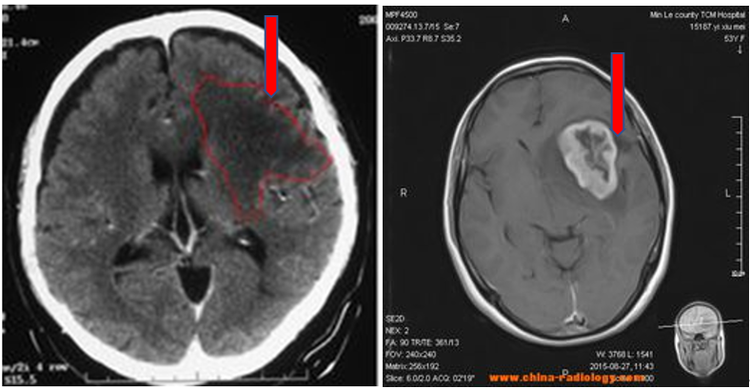

弥散张量成像是一种描述大脑白质纤维的新方法。能显示肿瘤与神经纤维束的关系,了解病变造成的白质纤维束受压移位、浸润与破坏;术者可以获得更多的信息,优化手术方式及指导手术入路,并在手术中权衡肿瘤切除范围与功能区神经功能的保护,最大范围切除肿瘤同时避免重要的纤维束损伤,从而使患者获取最大的手术效益。